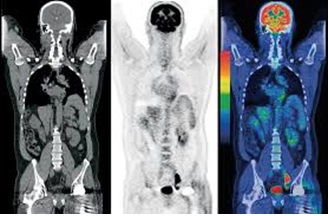

ПЭТ с метионином хорошо подходит для стадирования новообразований . Противопоказания ПЭТ противопоказана при наличии аллергии на радиофармпрепарат . Относительные противопоказания — беременность, нахождение на грудном вскармливании . Результаты могут быть ложными, если исследование выполнялось в скором времени после операции или лучевой терапии .

ПЭТ/КТ с метионином Метионин — безопасный для здоровья человека препарат, преимущественно использующийся при диагностике опухолей головного мозга . Он равномерно распределяется в мягких тканях организм . . .

Высокоточным методом диагностирования новообразований в головном мозге на сегодняшний день считается ПЭТ/КТ с метионином . Обследование дает возможность выявлять рак на ранних стадиях, что значительно улучшает показатели результативности лечения . Успешно применяется ПЭТ и для исследования сердечно-сосудистой системы и неврологических заболеваний .